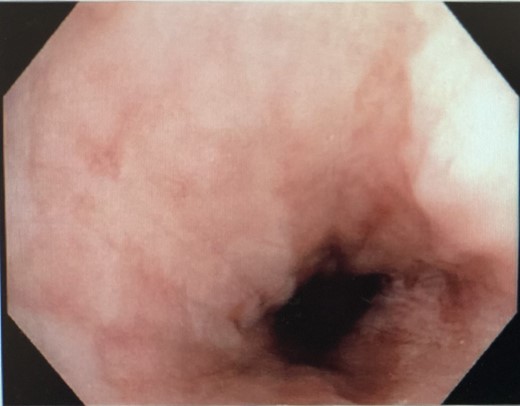

Interval gastroscopy in 2 weeks showed healing mucosal ischemia with slough from 27–30 cm (Fig. 3). Clear fluids were commenced and gradually upgraded to normal diet. Follow-up CT showed no contrast extravasation within posterior mediastinum (Fig. 4) and gastroscopy in 8 weeks showed healed esophagus.

Healing mucosal ischemia from upper, mid and distal esophagus.